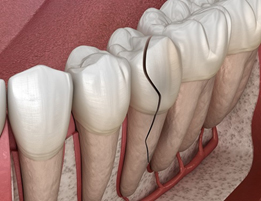

根管治療とは

根管治療とは、深い虫歯や歯の亀裂、外傷などの原因により、歯の根の中の歯髄(神経や血管など)が炎症や感染を起こした際に施す治療法です。歯髄が生きている場合は、冷たい水や熱いものが強くしみたり、ズキズキと強い痛みがあったり、歯と歯を咬み合わせられない程の痛みが出ます。これは「急性歯髄炎」という状態で、その場合は早急に根管治療を行わないと痛みが取れません。

また、上記のような状態を放置していると、歯髄が壊死・感染を引き起こし、根管を通じて、歯を支えている歯槽骨に炎症・感染が波及する場合があります。これは「根尖性歯周炎」という状態で、歯肉が部分的に少し腫れたり、咬合痛がでることがあります。上記の急性歯髄炎のような強い痛みが出ない場合がありますが、早急に根管治療を行わないと、歯槽骨内の感染が拡大し、悪い場合は抜歯に至るケースもあります。

根管は細く複雑な形状をしており、歯によって根管の数が複数ある場合があります。そのため根管治療は、非常に難しく、高い精度が求められる治療法と言えます。